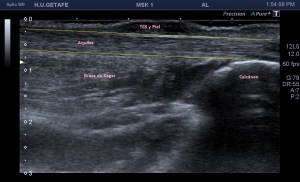

Normalidad, en la imagen 1 y 2 ves un aquiles normal.

Las imágenes 1 y 2 son la normalidad, es lo que casi nunca solemos ver en este tipo de estudios, pero en ocasiones sí, y como además cuando realizamos este protocolo, siempre es recomendable explorar lado contralateral, podemos muchas veces comparar la región patológica con la normal. El aquiles lo estudiamos siempre en toda su longitud, desde la inserción hasta su origen, en eje corto y en eje largo. Fijándonos bien en toda la ecoestructura posterior de la pierna y estudiando la profundidad de la grasa de Kager.

Las fibras del tendón son alargadas, lineales, tensas con las flexión dorsal.

Ojo con la anisotropía, la hipoecogenicidad producida el ligero cambio de angulación del tendón cuando inserta en el calcáneo posterior…La clave, hiperflexión dorsal, mucho gel y amoldar la posición de la sonda para estudiar estas fibras insercionales.